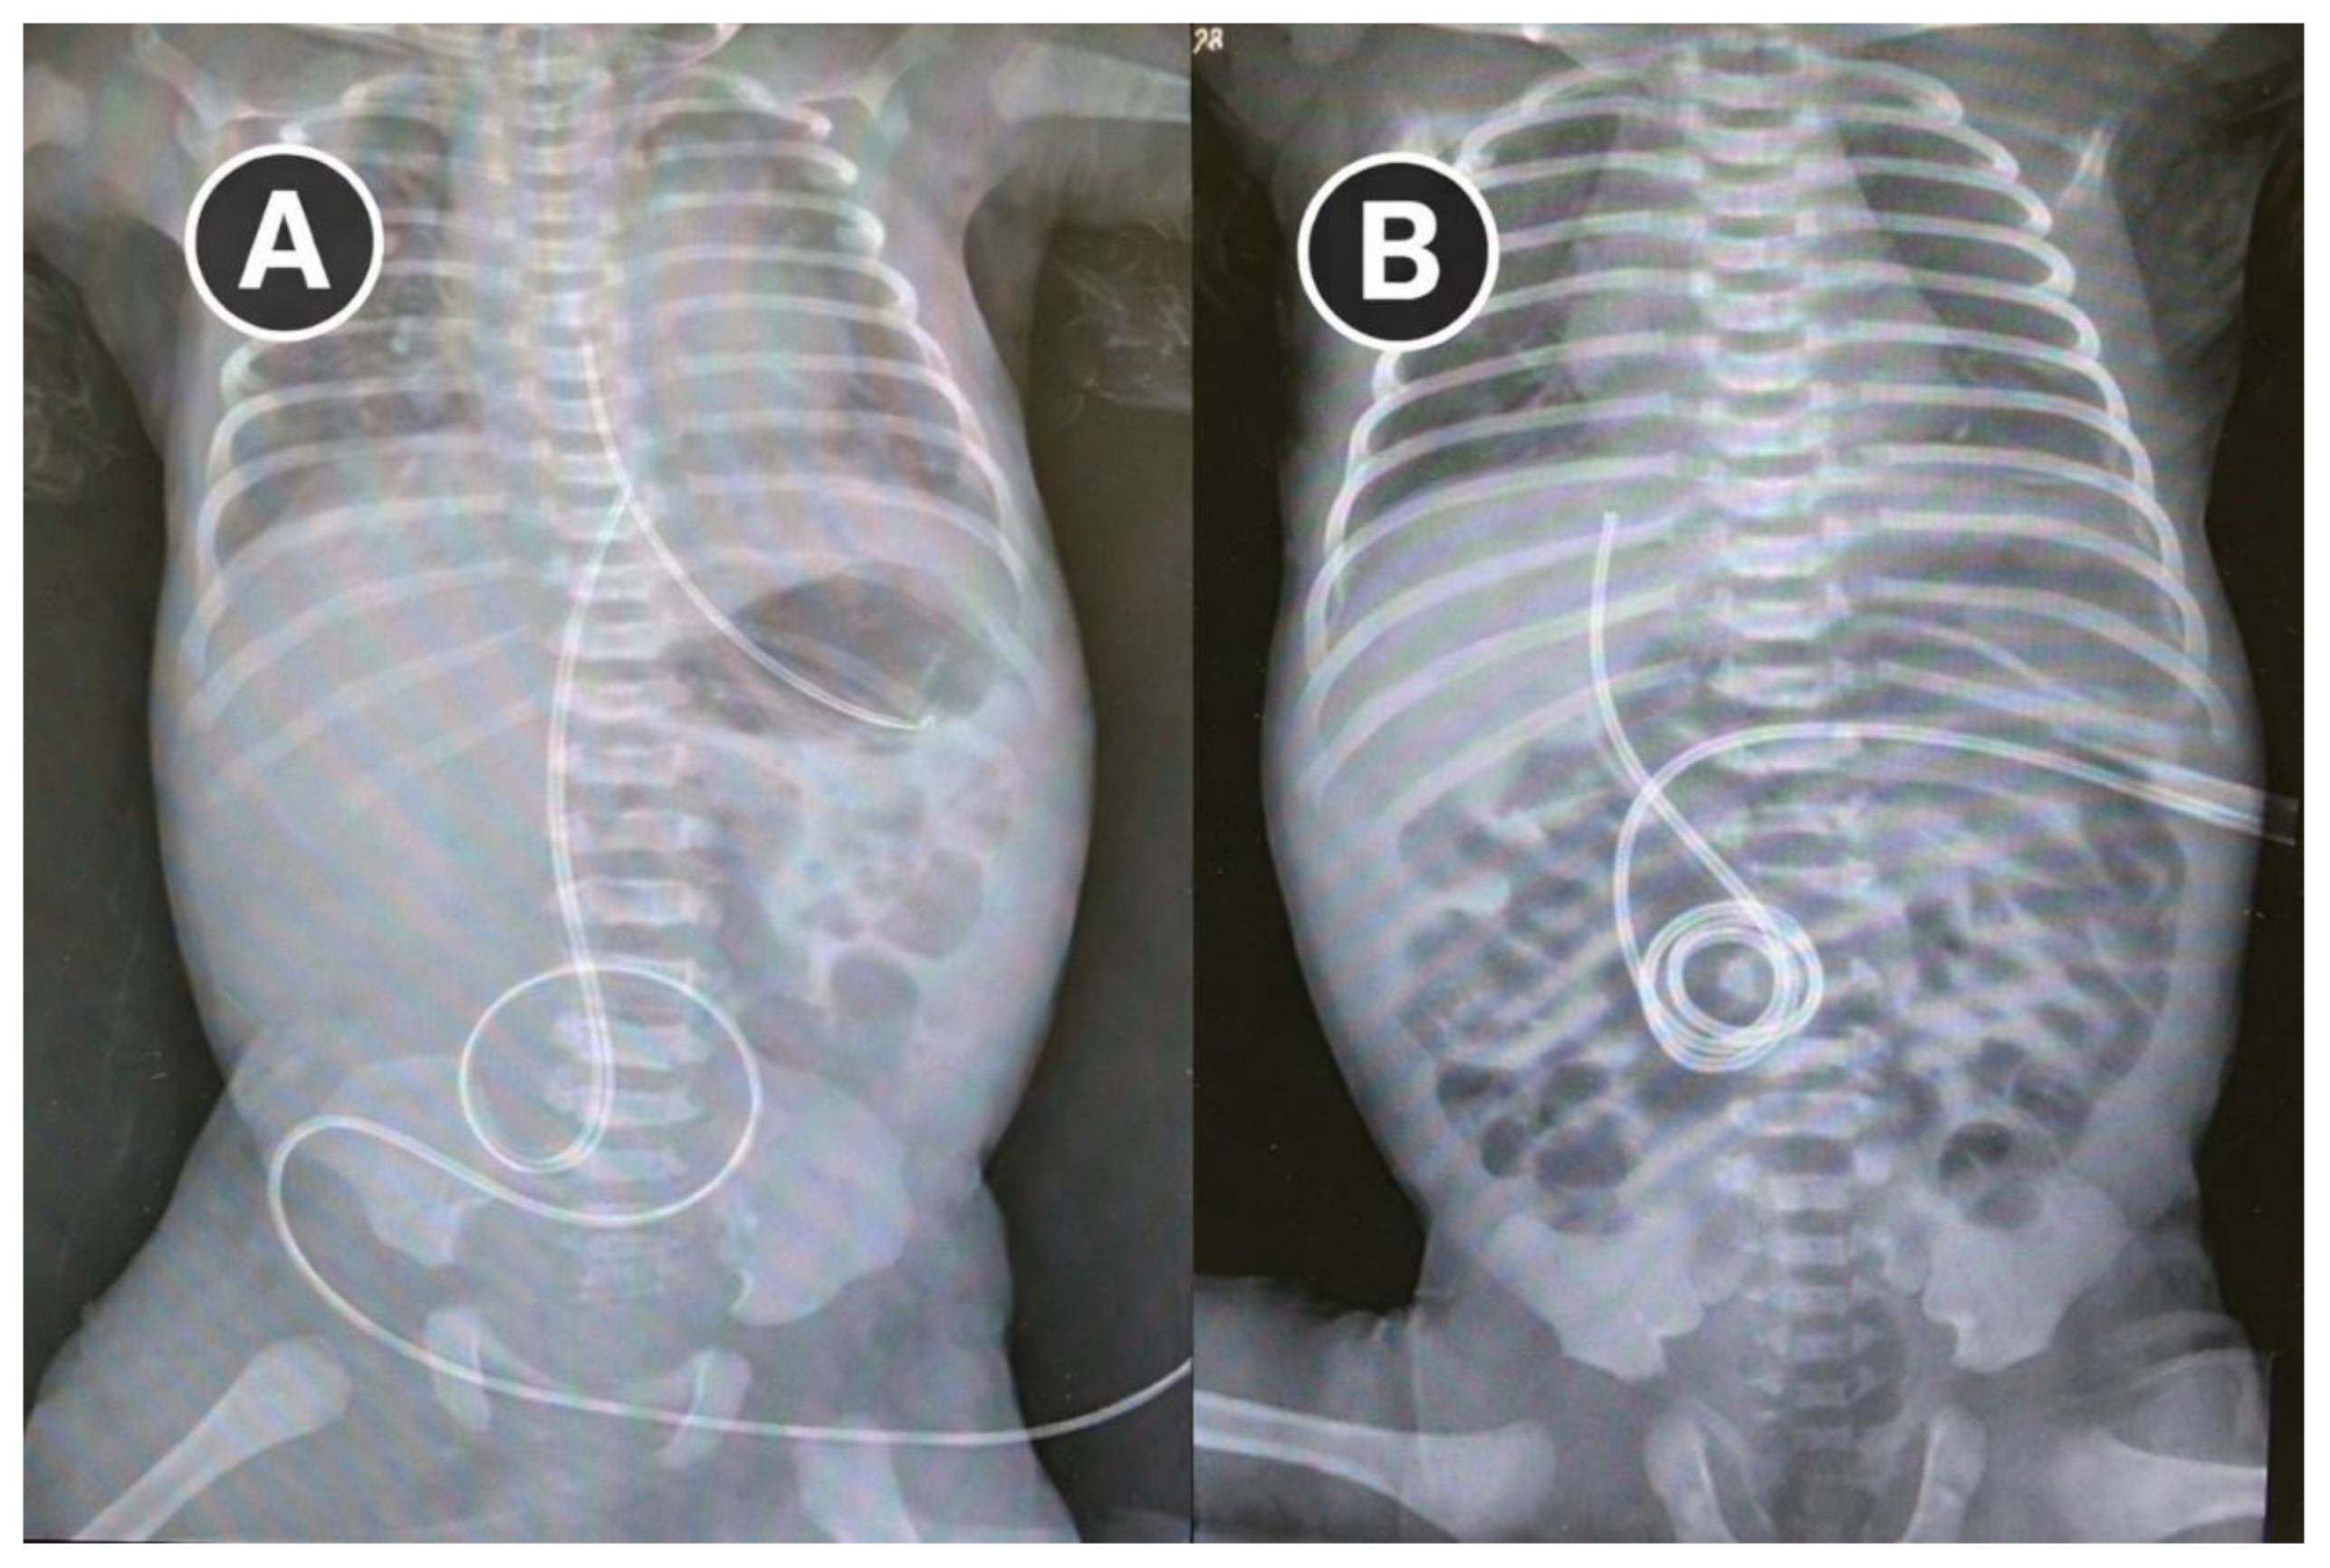

After 21 days of maternal ETI therapy, vaginal delivery occurred at 36+2 weeks without complications. The infant passed meconium shortly after birth, had an uncomplicated transition, and required no surgery. Serial abdominal radiographs over the first four days showed progressive resolution of bowel distension (Figure 2).

Figure 2. Progressive increase in bowel gas within the intestinal loops in a neonate with uncomplicated meconium ileus. Radiograph A was obtained a few hours after birth, following placement of a nasogastric tube and an umbilical catheter, while radiograph B was acquired 3–4 days later, showing progressive intestinal gas filling.